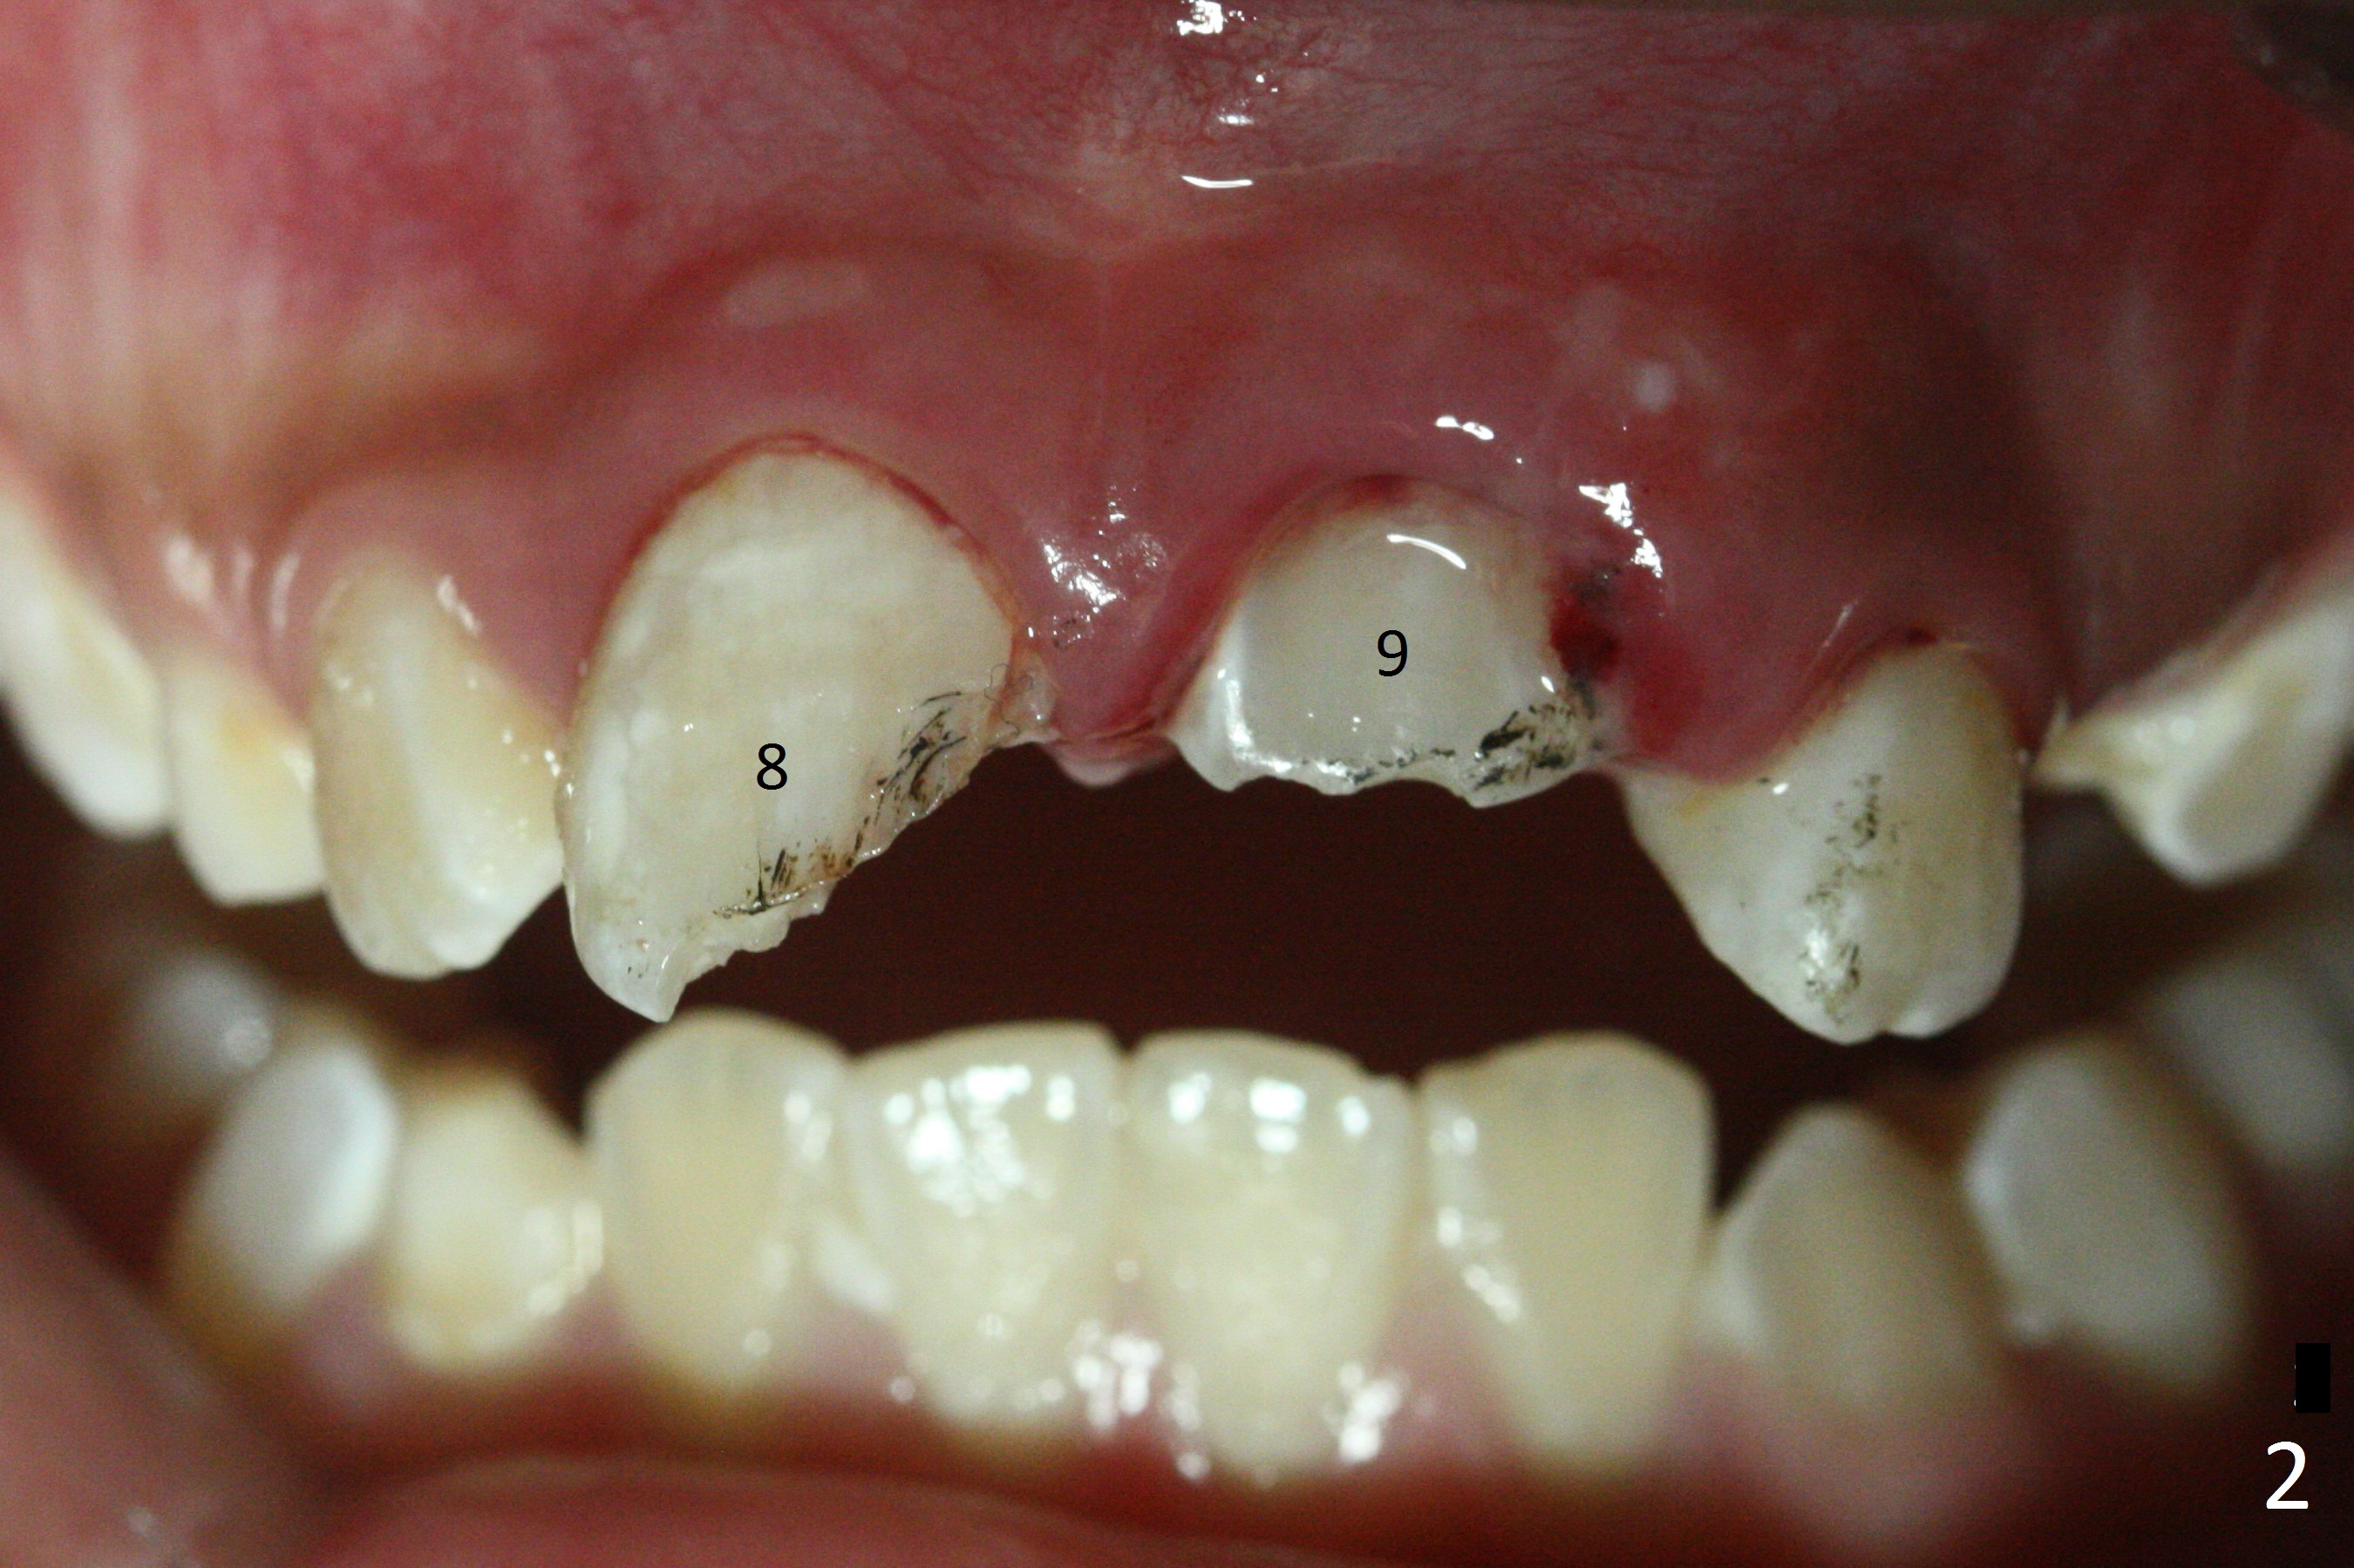

A 10-year-old boy has had Class II Division II malocclusion (Fig.1 impression taken 1 year earlier). He is brought to clinic the 2nd day after a bike accident. The tooth #8 fractures (Fig.2-4) with mesial pulpal horn exposure (Fig.3 *, while #9 intrudes. After debridement of the affected teeth (Fig.5), the exposed pulpal tissue is resected (partial pulpotomy to keep the tooth vital to finish root and apex development) and the pulpal horn is filled by MTA at #8 (Fig.6 *). The tooth #8 is restored with composite (Fig.7 C). Forceps fail to extrude the tooth #9. His parents are reluctant to accept orthodontic extrusion, which is accomplished by Dr. Shaughnessy 2 days later (Fig.8,9). The patient will leave for China in 2 days and will return in a month.